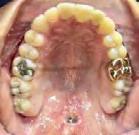

Estudios tomográficos en los cuales se observa tumoración expansiva a piso nasal de 3 centímetros de diá metro aproximadamente isodensa a tejidos blandos en zona de pala dar blando (Figura 3A y 3B). Motivo por el cual se decidió realizar biopsia incisional (Figura 4A , 4B y 4C) obte niendo un diagnóstico de Adenocar cinoma de células basales en paladar blando (Figura 5) con el cual se rea lizó referencia al centro oncológico naval para su seguimiento y trata miento. Actualmente se encuentra en tratamiento de quimioterapia.

Figura 4. A. Marcaje con bisturí de la muestra a tomar. B. Lecho quirúrgico de la muestra tomada. C. Afronte de la herida. A B C